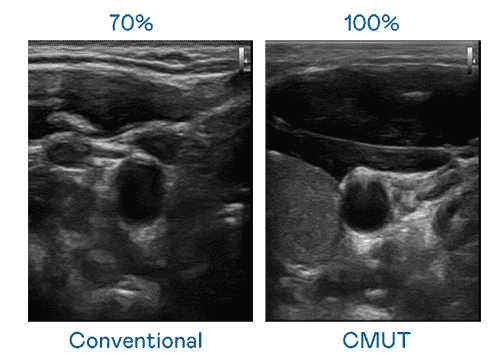

CMUT 技术是一种用电容式微机电元件来产生超音波讯号的技术。。。与传统 PZT 压电式技术相比,,,CMUT 频宽增加 30%,,更宽频的超音波讯号让影像解析度大幅提升,,,,是实现高影像品质医疗超音波扫描、、、、促进精准医疗发展的关键技术。。。

大频宽带来超清晰影像

超音波影像的解析度高低,,,首先取决于探头能发出的讯号频宽。。。。传奇国际 CMUT 可提供高清晰的超音波讯号,,提供高频宽、、高灵敏度、、、影像纹理细节更高的超音波影像,,协助医护人员缩短影像判读时间及利用精准的医疗影像进行诊断。。